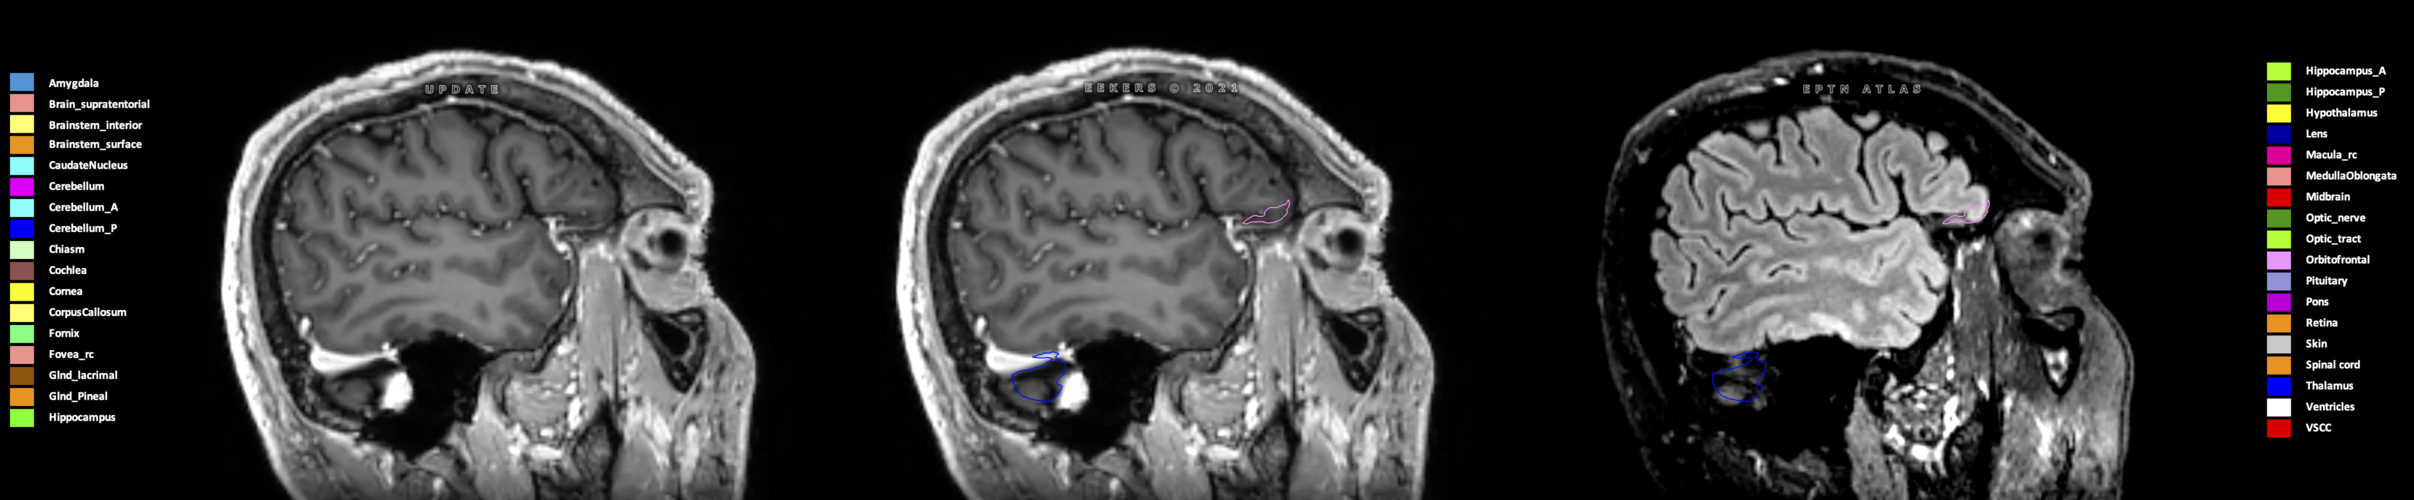

Eekers et al. have published an international neurological atlas for contouring of organs at risk in consensus with the European Particle Therapy Network (EPTN) in 2018 and an update in 2021. The purpose of this consensus atlas is to decrease inter- and intra-observer variability in delineating OARs relevant for neuro-oncology.

Included are all OARs known to be relevant for radiation-induced toxicity in neuro-oncology: brain, brainstem (midbrain, pons, medulla oblongata), chiasm, cerebellum (anterior & posterior), cochlea, cornea, hippocampus (anterior & posterior), hypothalamus, lens, lacrimal gland, optic nerve, pituitary, skin, and vestibular & semicircular canals. To further facilitate research on cognition, vision and radiological changes after irradiation of the brain, potential clinically-relevant OARs are included: amygdala, caudate nucleus, cerebellum (anterior & posterior), corpus callosum, fornix, macula, optic tract, orbitofrontal cortex, periventricular space (PVS), pineal gland, and thalamus.

Three-dimensional delineation of the 25 consensus OARs for neuro-oncology are shown on CT (WW/WL 120/40, 3000/600), 3T MR images, (T1Gd, T2FLAIR 1mm) and 7T MR (MP2RAGE 0.7 mm). All are presented in transversal, sagittal and coronal view.